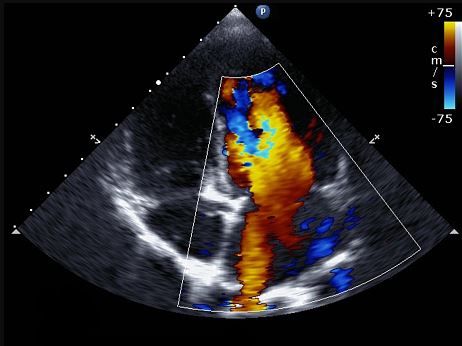

- ECOGRAFIA PLEURAL Y PULMONAR